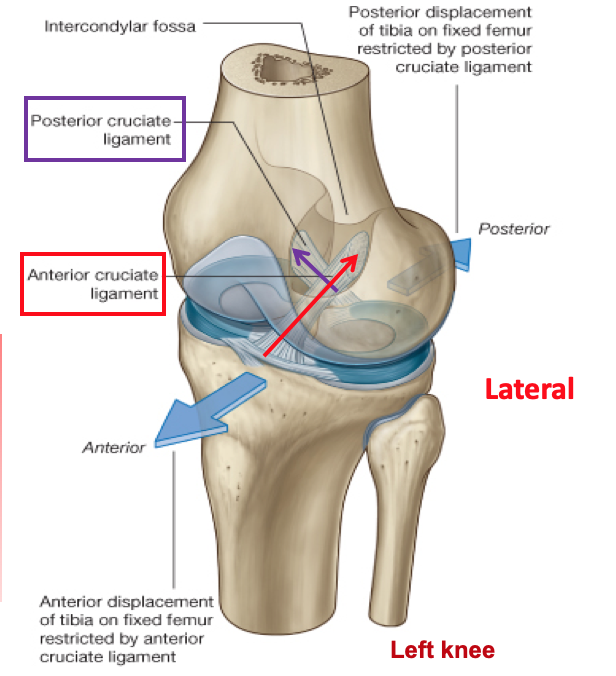

What are the ‘intra-articular’ ligaments of the knee?

cruciate ligaments

there is an anterior and a posterior cruciate ligament

Label the 2 ligaments

What is their main function?

they sit in a crossed fashion inside the joint and prevent lateral displacement of the femur and tibia

What is the origin and attachment of the posterior cruciate ligament?

it attaches to the posterior intercondylar region of the tibia

it travels supero-anteriorly to insert onto the medial femoral condyle

What is the attachment and insertion of the anterior cruciate ligament?

it attaches to the anterior intercondylar region of the tibia

it travels supero-posteriorly to attach to the lateral femoral condyle

Which cruciate ligament is stronger?

the posterior cruciate ligament is STRONGER than the anterior cruciate ligament

Label the cruciate ligaments as if looking down inside a left knee